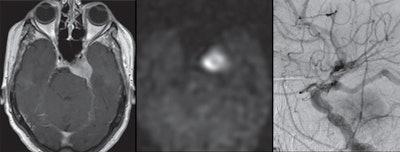

Arterial spin labeling (ASL) MRI could become a viable complement to digital subtraction angiography (DSA) in screening for hypervascular meningiomas and determining the need for presurgical intervention, according to a study published in the November issue of the American Journal of Roentgenology.

If ASL-MRI can detect increased tumor blood flow in meningiomas that have heightened tumor vascularity on DSA -- also known as tumor blush -- clinicians will have a much better handle on which patients might benefit from preoperative embolization.

"We hypothesized that increased ASL signal intensity within meningiomas will correlate with the presence of tumor blush on DSA, suggesting that this imaging modality can reliably identify meningiomas that are hypervascular," the authors wrote.

Based on ASL images, two independent readers detected all 39 meningiomas, which had a mean size of 9.8 (± 12.2) cm2. Meningiomas with tumor blush had a mean size of 13.4 (± 2.4) cm2, compared with a mean size of 2.7 (± 2.4) cm2 for meningiomas with no tumor blush. Using DSA, the readers also were able to discern 26 lesions (67%) with tumor blush and 13 lesions (33%) with no tumor blush.

As one might expect, mean normalized tumor blood flow was significantly higher in the tumor blush group (4.7 ±1.1), compared with the lesions with no tumor blush (1.5 ±1.1) (p < 0.001). When the researchers used the benchmark of 2.7 for normalized tumor blood flow, they achieved sensitivity of 88% and specificity of 67%. However, they declined to endorse the cutoff of 2.7 as "a single threshold for routine use," because of the study's small sample size.

"Nonetheless, we have shown that meningiomas that have tumor blush on DSA have significantly higher normalized tumor blood flow than those without tumor blush," Mayercik and colleagues concluded. "Thus, ASL-MRI has potential to be used as a screening tool for the selection of candidates who may benefit from preoperative embolization."